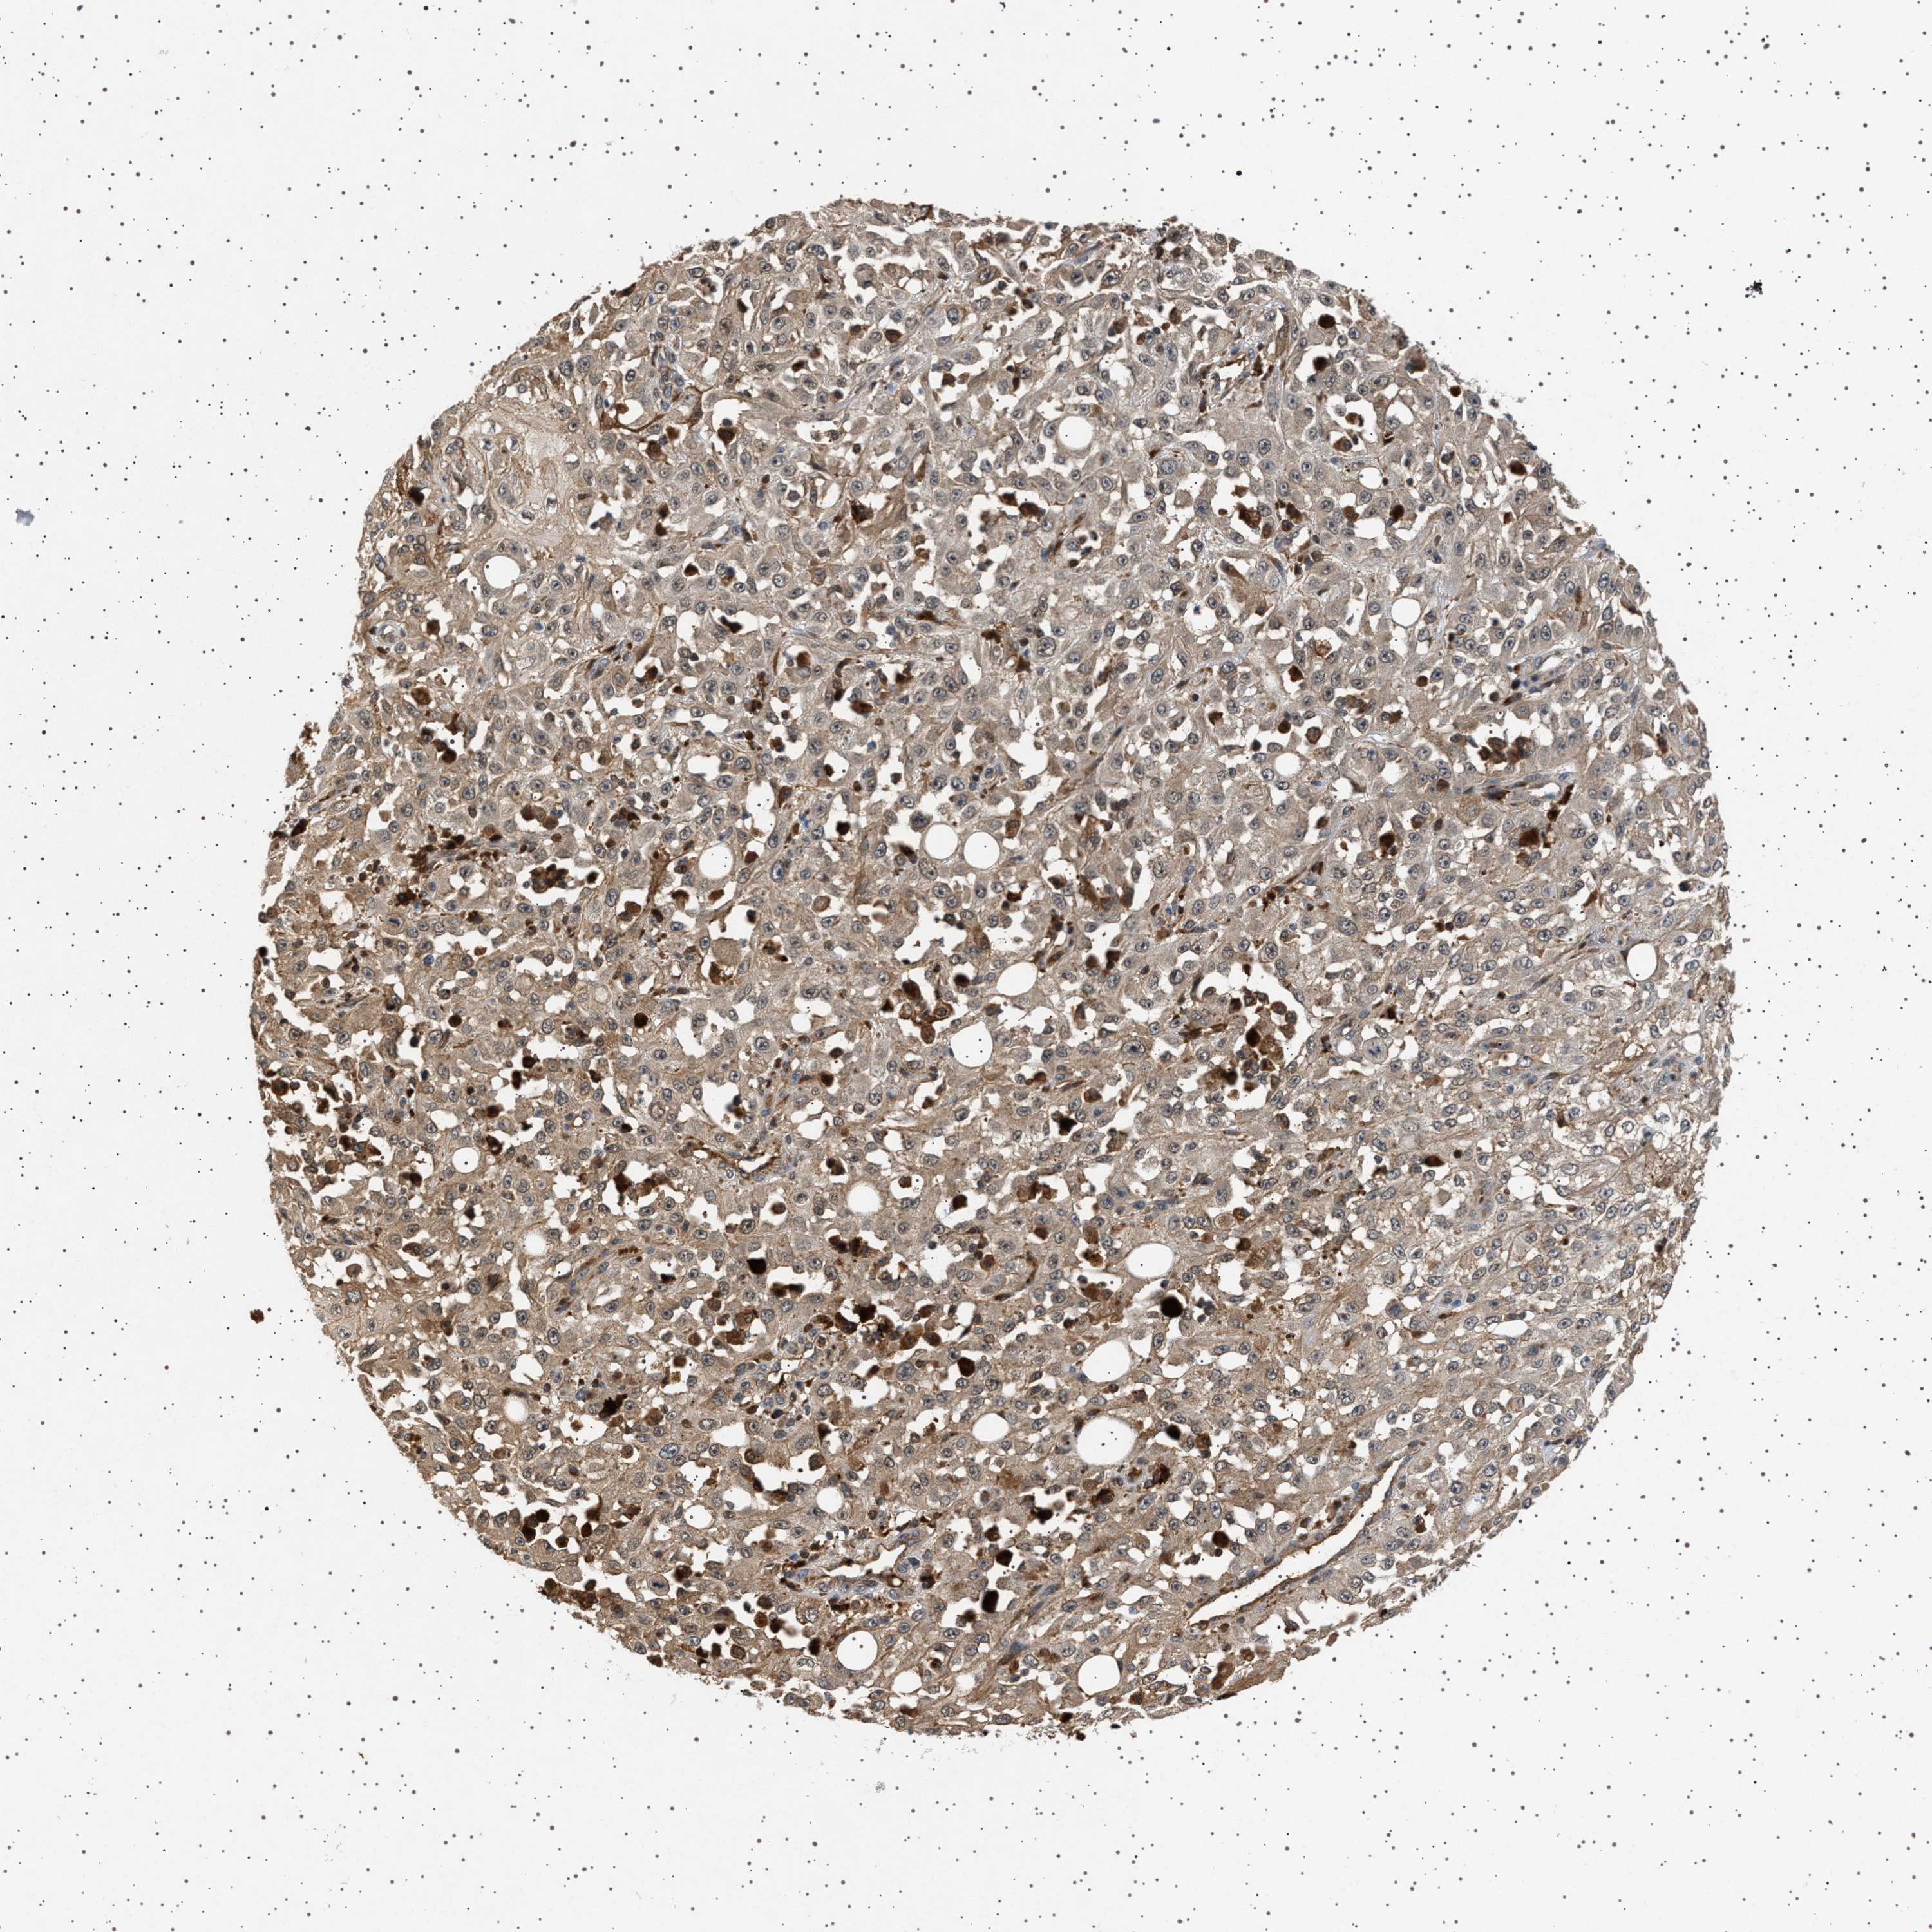

Basal cell and squamous cell cancer

SKIN CANCER - Protein expressioni

A mouse-over function shows sample information and annotation data. Click on an image to view it in a full screen mode. Samples can be filtered based on level of antibody staining by selecting one or several of the following categories: high, medium, low and not detected. The assay and annotation is described here.

Each image is clickable and will lead to virtual microscopy that enables deeper exploration of all samples and also displays staining intensity scores, fraction scores and subcellular localization as well as patient and tissue information for each sample.

Antibody HPA021390

Staining

High

Medium

Low

Not detected

Intensity

Strong

Moderate

Weak

Negative

Quantity

>75%

75%-25%

<25%

None

Location

Nuclear

Cytoplasmic/membranous

Cytoplasmic/membranous,nuclear

Squamous cell carcinoma, NOS

Squamous cell carcinoma, metastatic, NOS